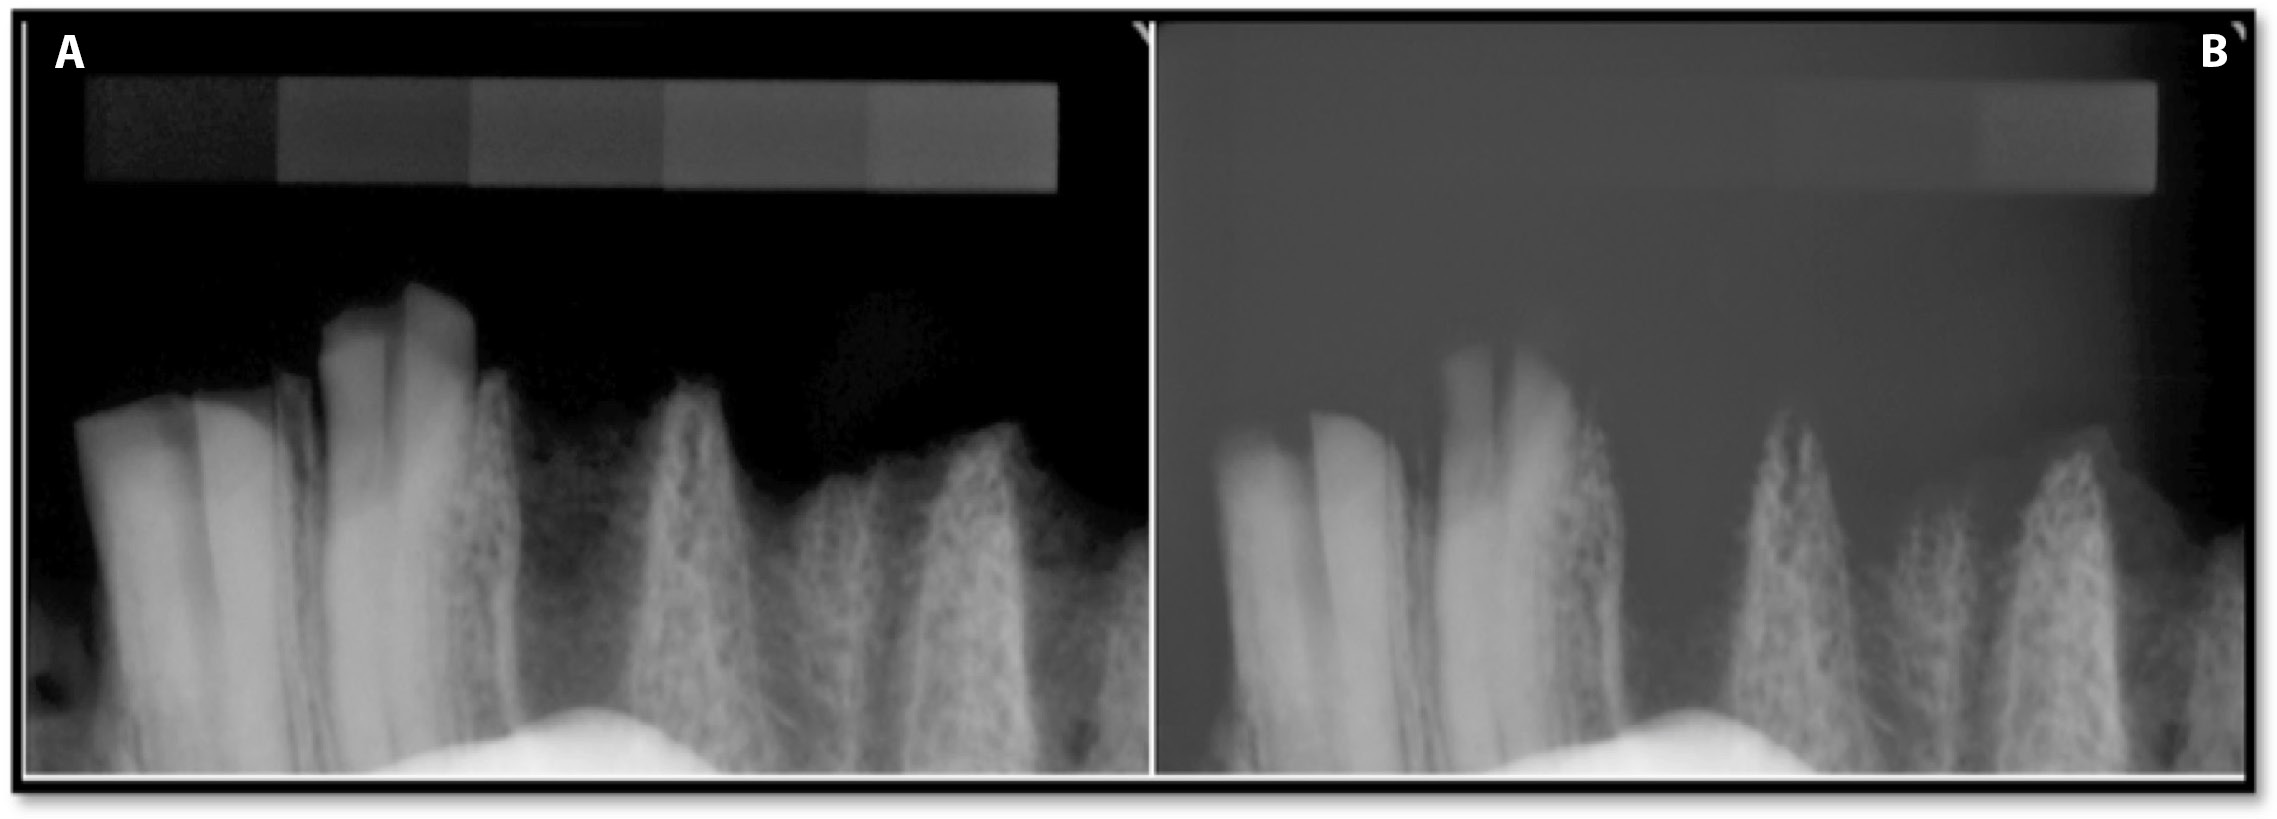

According to the study design, the 1st stage consisted in collecting values of optical density for all exposure times after image registration in the patients’ charts and without the image corrections being subjected to analysis on the PC connected to the Dixi3 sensor (Group A). The values of optical density in Group A are presented in Table 1 and Figure 5. The data (Group A) showed the influence of exposure time on optical density when the image optimization algorithm was active (default software setting). When the exposure times ranged from 0.05 s to 0.125 s, the optical density values measured along all phantom steps decreased with an increase in exposure time. The largest optical density decrease was observed for step 1 – 31.7% (14.2 ±2.2 at 0.05 compared to 9.7 ±1.4 at 0.125) – and the smallest was for step 9: 0.8% (234.0 ±1.9 at 0.05 compared to 232.1 ±1.2 at 0.125). At exposure times of 0.05–0.125 s and over the whole optical density range, the differences between the degrees of the pattern were sufficient, i.e., the images had sufficient contrast. The Group A radiographs of bone specimen captured with exposure times of 0.125 s and 0.2 s are presented in Figure 6. The excessive exposure time caused image disturbances of the objects with an optical density of less than 50. On the images captured with an exposure time of 0.16 s, the differences between the background and steps 1 and 2 of the pattern were blurred and no considerable differences between these ROIs were noticed. With an exposure time of 0.2 s, the differences were blurred not only between the background and steps 1 and 2, but also between the background and steps 3 and 4. Therefore, it can be stated that an object with low radioabsorption becomes imperceptible at exposure times of 0.16 s or 0.2 s. A comparison of the bone specimen radiographs that were captured with exposure times of 0.125 s and 0.2 s displayed a blurred difference between the background and the object at a longer exposure time (Figure 5).

When analyzing and comparing images, it should not be forgotten that the software usually compensates for variations in exposure parameters with automated optimizing algorithms. The option (algorithm) of automated adjustment, which corrects a digital image, is also included in the Dimaxis software that was used in this study. The default application of an optimization algorithm significantly reduces the differences between exposure times if they are in the range of 0.05–0.125 s. The use of longer exposure times (0.16 s and 0.2 s) highlights the limitations of the software and the sensor used in this study, as it caused image disturbances of objects with an optical density of less than 50. Because an object with low radioabsorption becomes imperceptible at exposure times of 0.16 s or 0.2 s, those radiographs were recognized as “lighted.” A similar selection was made in the article by Morea et al. due to the ghost images which were produced by an exposure time beyond the latitude of the sensor.16 Overexposure of the 0.16-second and 0.2-second images can also be caused by the lack of a soft-tissue-equivalent absorbing part of the radiation between the X-ray beam and sensor. The soft tissue model was not included in the current study. This assumption is confirmed in Figure 7, Figure where the operation of the algorithm is visible and makes the first-degree pattern and a thin alveolar plate invisible.